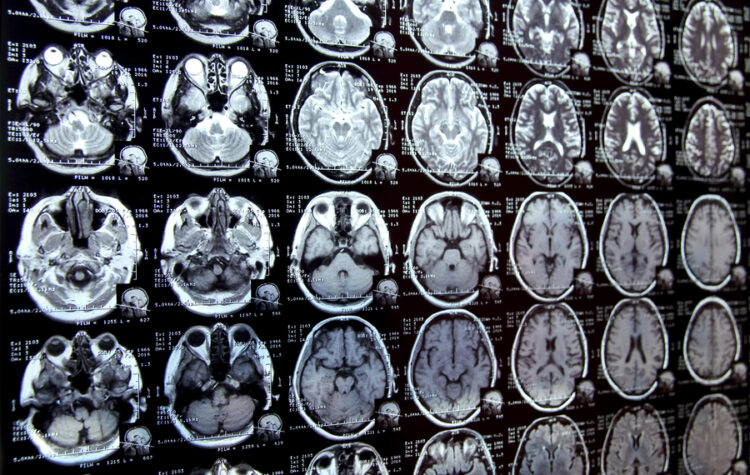

By enabling rapid annotation of areas of interest in medical images, the tool can help scientists study new treatments or map disease progression.

“ScribblePrompt” is an interactive AI framework that can efficiently highlight anatomical structures across different medical scans, assisting medical workers to delineate regions of interest and abnormalities.